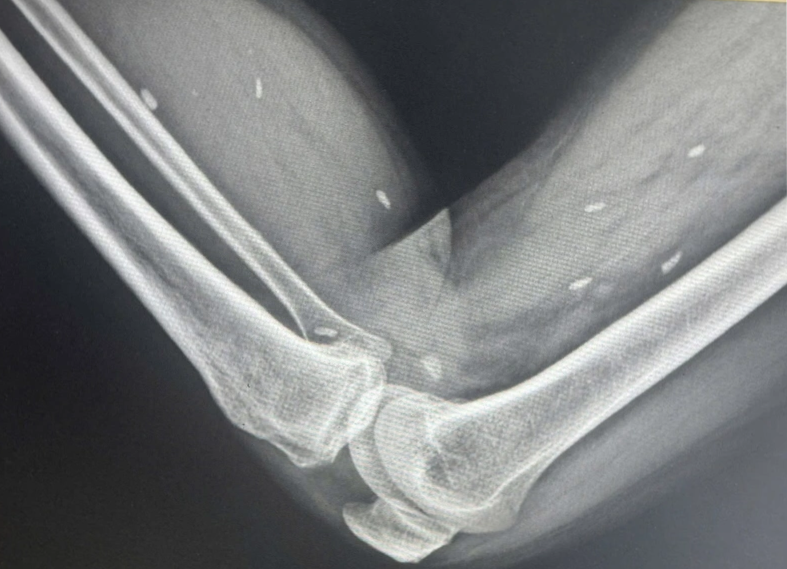

Kết quả cho thấy nhiều kén sán có kích thước tương đương hạt gạo, nằm rải rác trong các mô mềm vùng xương đùi và cẳng chân. Bác sĩ nhận định đây là hình ảnh điển hình của tình trạng nhiễm kén sán.

Ông H. cho biết, có thói quen ăn đồ sống. Sau khi được chẩn đoán nhiễm kén sán, người bệnh đã được chuyển lên tuyến trên để tiếp tục theo dõi và điều trị chuyên sâu.